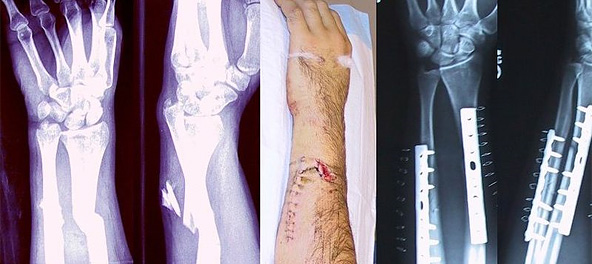

Перелом кости — полное или частичное нарушение целостности кости при нагрузке, превышающей прочность травмируемого участка скелета. Переломы могут возникать как вследствие травмы, так и в результате различных заболеваний, сопровождающихся изменениями в прочностных характеристиках костной ткани.

Основные принципы лечения переломов не изменились с эпохи античности, хотя современная хирургия и позволила восстанавливать анатомическую структуру костей при сложных, вколоченных, многооскольчатых переломах, переломах, неправильно сросшихся, без восстановления нормального положения кости, и многих других видах травм

Так, например, перелом шиловидного отростка лучевой кости, называется переломом Коллеса. Также к довольно известным типам травм верхней конечности относятся перелом Монтеджа, возникающий при переломе локтевой кости в верхней трети и вывихе головки лучевой кости с повреждением ветви лучевого нерва, и перелом Голеацци, представляющий собой перелом лучевой кости в нижней трети с разрывом дистального радио-ульнарного сочленения и вывихом в этом суставе.